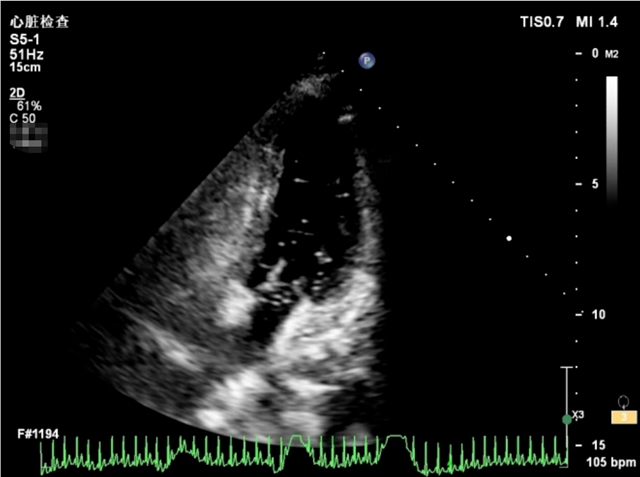

辗转找到了西南医科大学附属中医医院胸心外科邓志刚教授。入院后,邓志刚教授详细询问了病史及综合分析后,怀疑是心脏上的问题,便为其完善了心脏彩超,结果发现心脏竟然有个“小眼”。

为进一步明确病因,再次完善了发泡试验及食管心脏彩超检查,确诊:卵圆孔未闭。

后续医生顺利为小李实施了食管超声引导下的卵圆孔未闭封堵术,术后第1天复查心脏彩超显示“小心眼”消失,封堵完全,术后第2天出院,术后1个月复查的时候头痛症状明显缓解。